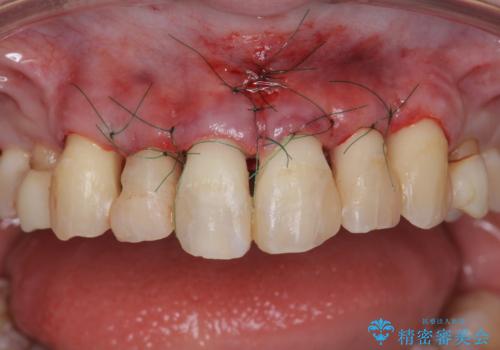

まず虫歯を拡大鏡、マイクロスコープ下で丁寧に取り除き歯肉縁下の虫歯を歯周外科により解決したのち、ジルコニアクラウン製作を行っていきます。

丁寧な虫歯の除去・歯周組織の整備、適合の良い精密なセラミッククラウンの製作といった丁寧な治療の積み重ねが良好な治療結果を得ることにつながります。